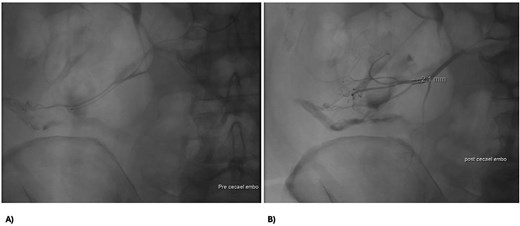

A 73 year-old male presented to our tertiary hospital with a three day history of major colonic bleeding, while on therapeutic warfarin for a metallic aortic valve. Other medical history included laparoscopic cholecystectomy, Parkinson’s disease, and a normal colonoscopy 12 months prior. Computed tomographic mesenteric angiography demonstrated active contrast pooling within the caecum and appendiceal base (Fig. 1). He underwent successful interventional radiology guided angioembolization of a branch of the ileocolic artery, using a gel embolic injection (Fig. 2).

Abdomen angiography demonstrating successful ileocaecal angioembolization with an embolic gel.